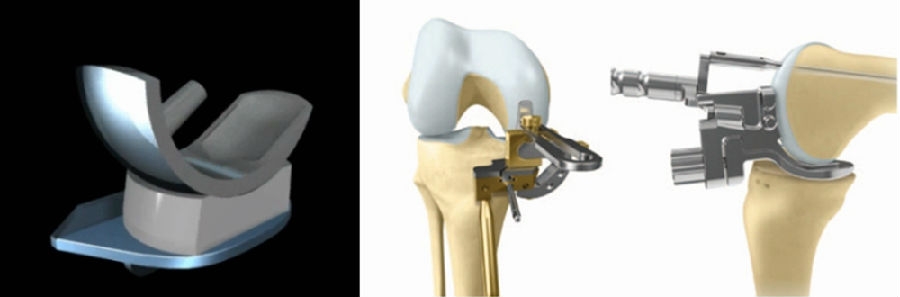

活动平台单髁(OUKA)优秀的设计,辅以友好的工具MP,目前已经取得了非常好的一些临床疗效。

尽管MP工具已经比较优秀,但是在临床实际操作过程中,MP工具还是存在一些偏差。比如股骨低头不够,胫骨平台后倾偏小或偏大,胫骨覆盖不足,股骨胫骨假体之间的相对垂直距离过大,胫骨过度外旋,胫骨过度内旋,后交叉韧带部分损伤等问题。

未来如何实现单髁更精准、更微创,可能需要不同维度的解决方案。首先就是机器人,目前机器人比较火,因为其精准度比较高,但是它需要购置专用设备,价格昂贵,而且不利于在基层开展,特别是在目前的经济环境下;同时机器人设备需要占据空间,术中需要专门的工程师配合,术中需要注册,手术时间相对延长等特点。

对于单髁来说,考虑的另外一个解决方案就是3D打印导板结合AI。其具有精准度较高,不需要购置专用设备,价格亲民,利于在基层开展,不需要额外的设备空间,不需要术中专门的工程师配合等特点。但是,同时术中需要清除软骨和贴附导板可能会导致手术操作时间相对延长。